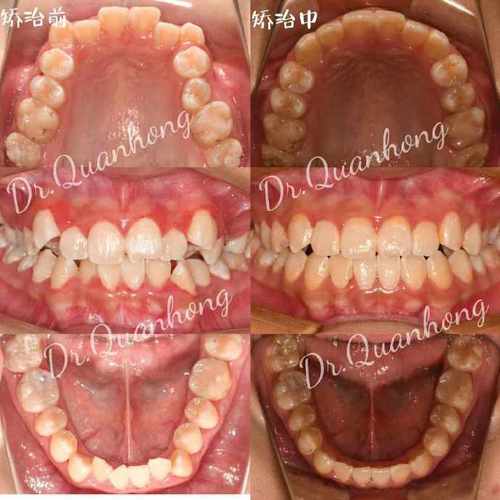

主动间隙关闭阶段(3-12个月,核心阶段)

此阶段通过矫治器(如滑动法关闭曲、种植支抗等)施加持续、轻柔的生物力,推动牙齿快速移动,前牙(切牙、尖牙)整体向远中移动,后牙(磨牙)向近中移动,同时保持垂直高度稳定,间隙变化图特征显著:前牙切端逐渐向拔牙侧移动,后牙近中面与对颌牙建立初步接触,间隙宽度每月缩小约1.0-1.5mm;牙槽骨改建活跃,压力侧可见骨吸收透射影,张力侧骨密度增高;牙根位置随牙齿移动调整,逐渐趋于平行。

精细调整阶段(12-18个月)

当间隙基本关闭后,进入细节优化阶段,医生通过调整弓丝转矩、更换细丝(如0.018英寸不锈钢丝)进行“轻力细调”,纠正牙齿的轻微扭转、转矩异常,建立稳定的咬合关系(如尖牙引导、组牙功能颌),间隙变化图显示:牙齿排列整齐,牙根平行,牙槽骨改建完成,密度均匀;牙龈形态逐渐恢复,若存在牙龈凹陷,可能需通过牙周手术或正畸牵引改善。